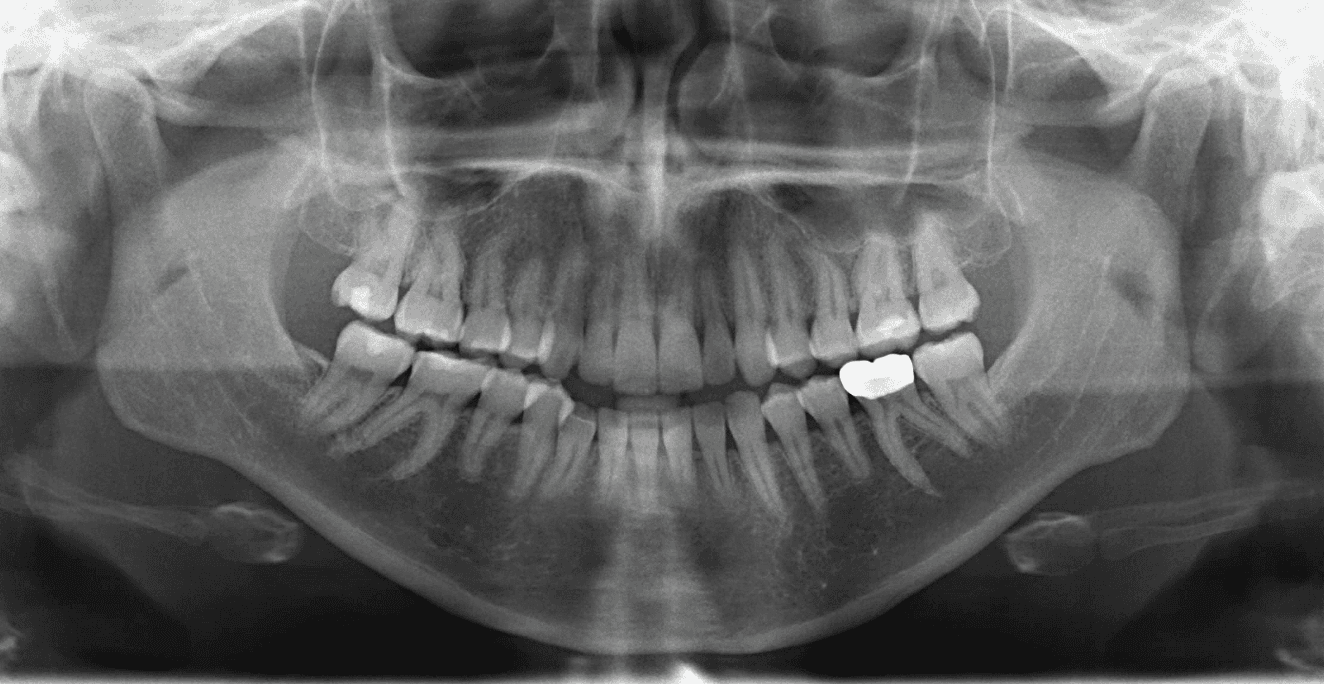

X-RAYS